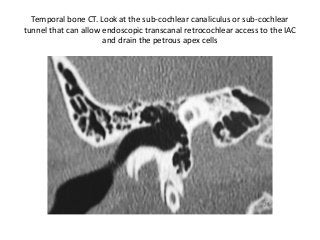

Temporal bone CT. Look at the sub-cochlear canaliculus or sub-cochlear

tunnel that can allow endoscopic transcanal retrocochlear access to the IAC

and drain the petrous apex cells